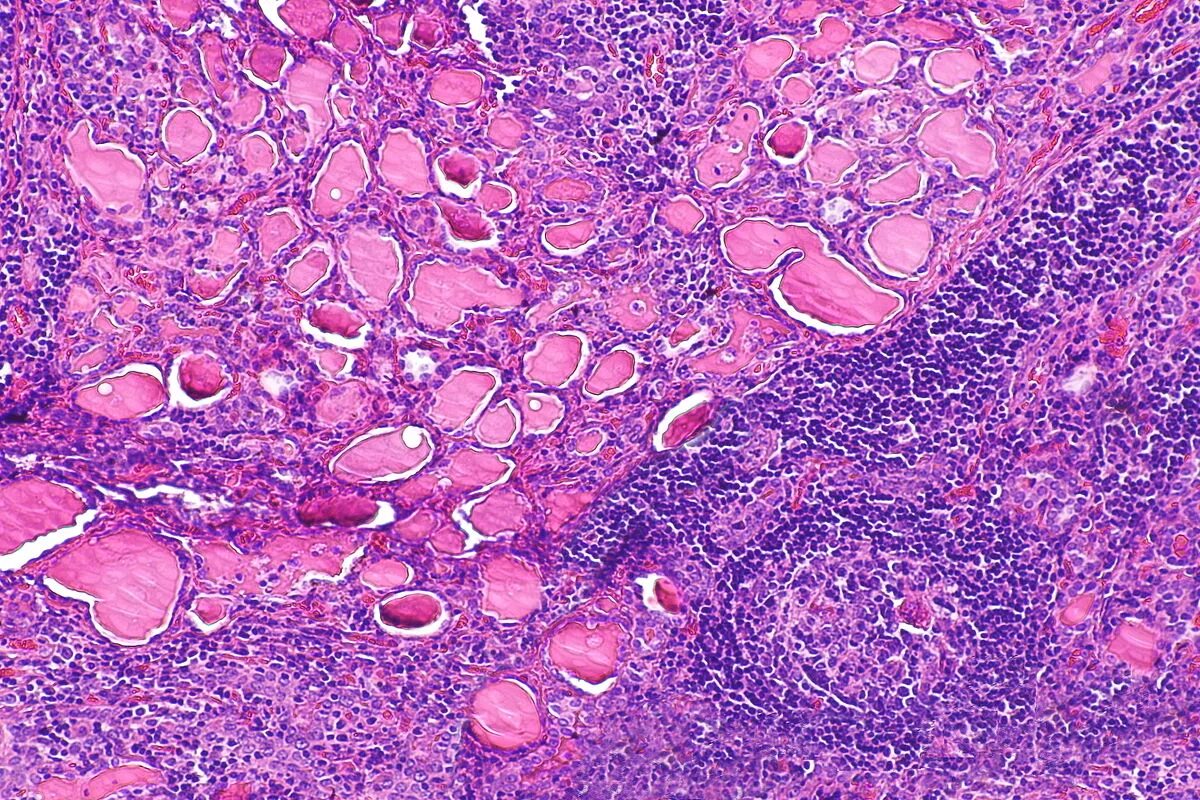

Гистология смешанный